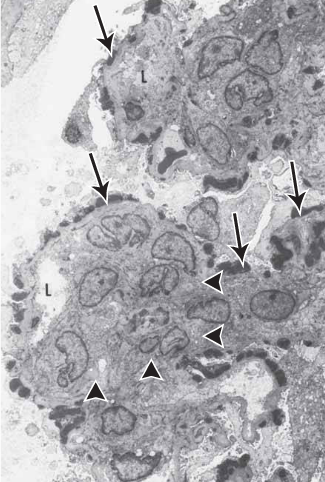

EM shows numerous subepithelial humps (arrows) and mesangial hypercellularity (arrowheads). Capillary lumina (L) are markedly narrowed

acute post infectious glomerulonephritis